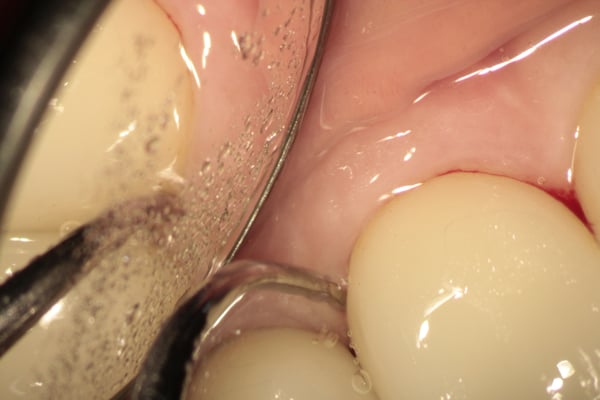

顕微鏡下で歯石を除去することは,様々なメリットがあり,ベテランならではの手技や考えもあります。

彼女の正確かつ的確なプロービング(歯周ポケットを計測すること)によって,大きな治療になる前に気付くことも多々あり,通院されている多くの患者さんの健康を水際で,また,第一線で守っています。

診査・診断

メインテナンス時に,様々な状態に気づくのは,経験を積んだ歯科衛生士ならではです。経験には、人生経験も含まれます。